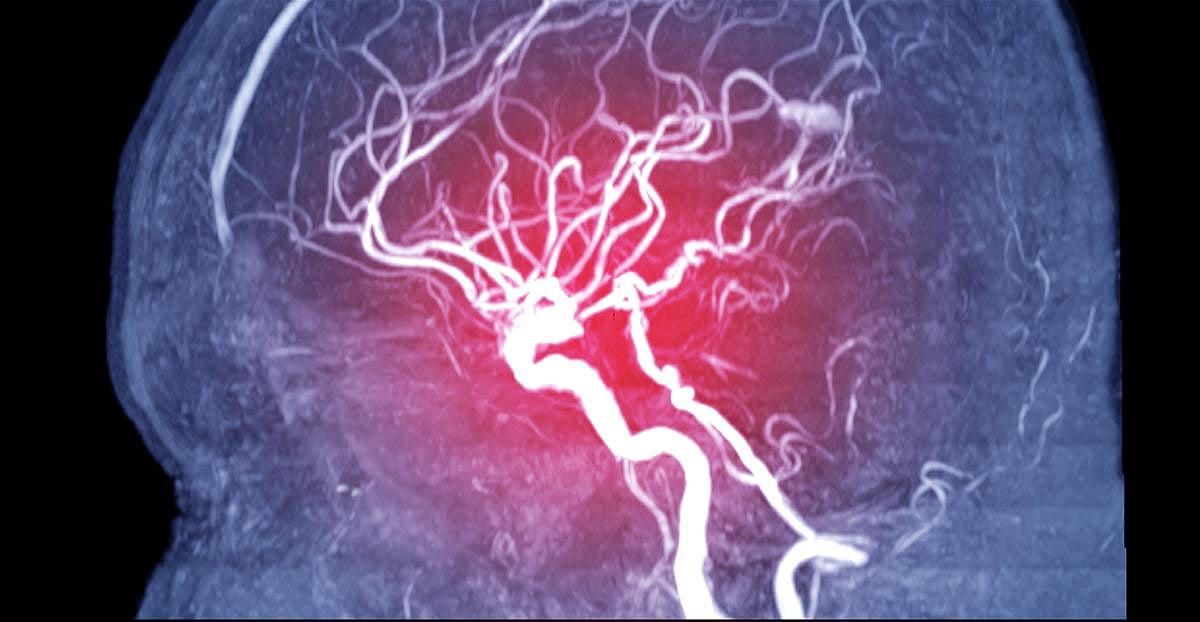

DBS involves surgical placement of electrodes to deliver electrical impulses to areas of the brain regulating specific activity. It is often used to treat control movement problems associated with Parkinson's disease.

The team proposed using DBS to stimulate a structure deep within the brain called the motor thalmus, a key hub of movement control. Because this had never been done before, they first tested it in monkeys, which have the same links as people between the motor cortex and muscles.